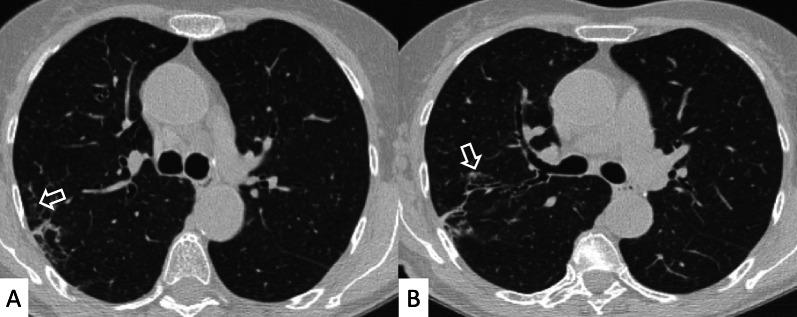

Connective tissue diseases (CTDs) include a spectrum of disorders that affect the connective tissue of the human body; they include autoimmune disorders characterized by immune-mediated chronic inflammation and the development of fibrosis. Lung involvement can be misdiagnosed, since pulmonary alterations preceded osteo-articular manifestations only in 20% of cases and they have no clear clinical findings in the early phases. All pulmonary structures may be interested: pulmonary interstitium, airways, pleura and respiratory muscles. Among these autoimmune disorders, rheumatoid arthritis (RA) is characterized by usual interstitial pneumonia (UIP), pulmonary nodules and airway disease with air-trapping, whereas non-specific interstitial pneumonia (NSIP), pulmonary hypertension and esophageal dilatation are frequently revealed in systemic sclerosis (SSc). NSIP and organizing pneumonia (OP) may be found in patients having polymyositis (PM) and dermatomyositis (DM); in some cases, perilobular consolidations and reverse halo-sign areas may be observed. Systemic lupus erythematosus (SLE) is characterized by serositis, acute lupus pneumonitis and alveolar hemorrhage. In the Sjögren syndrome (SS), the most frequent pattern encountered on HRCT images is represented by NSIP; UIP and lymphocytic interstitial pneumonia (LIP) are reported with a lower frequency. Finally, fibrotic NSIP may be the interstitial disease observed in patients having mixed connective tissue diseases (MCTD). This pictorial review therefore aims to provide clinical features and imaging findings associated with autoimmune CTDs, in order to help radiologists, pneumologists and rheumatologists in their diagnoses and management.

结缔组织病(CTDs)包括一系列影响人体结缔组织的疾病;它们包括以免疫介导的慢性炎症和纤维化发展为特征的自身免疫性疾病。肺部受累可能会被误诊,因为肺部改变仅在20%的病例中先于骨关节炎表现出现,且在早期阶段没有明确的临床发现。所有肺部结构都可能受累:肺间质、气道、胸膜和呼吸肌。在这些自身免疫性疾病中,类风湿关节炎(RA)的特征是普通型间质性肺炎(UIP)、肺结节和伴有空气潴留的气道疾病,而系统性硬化症(SSc)常表现为非特异性间质性肺炎(NSIP)、肺动脉高压和食管扩张。NSIP和机化性肺炎(OP)可见于多发性肌炎(PM)和皮肌炎(DM)患者;在某些情况下,可观察到小叶周围实变和反晕征区域。系统性红斑狼疮(SLE)的特征是浆膜炎、急性狼疮性肺炎和肺泡出血。在干燥综合征(SS)中,HRCT图像上最常见的表现是NSIP;UIP和淋巴细胞间质性肺炎(LIP)的报道频率较低。最后,纤维化NSIP可能是混合性结缔组织病(MCTD)患者中观察到的间质性疾病。因此,本图像综述旨在提供与自身免疫性CTDs相关的临床特征和影像学表现,以帮助放射科医生、呼吸科医生和风湿病科医生进行诊断和管理。